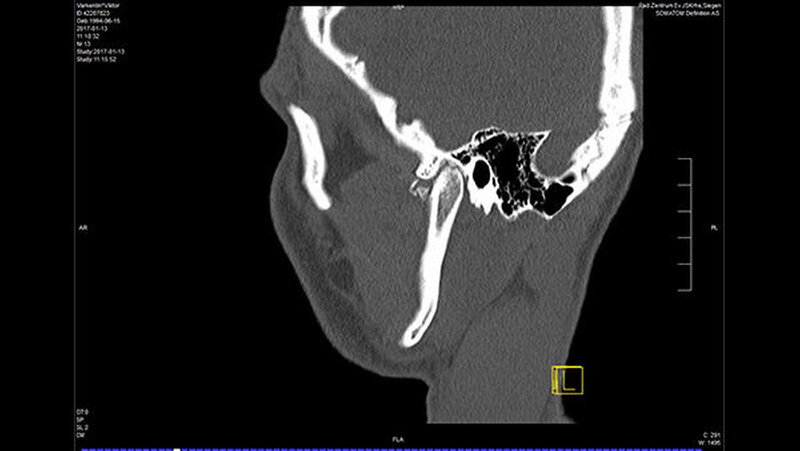

In der Folge entwickelte sich binnen fünf Monaten eine absolute Mundöffnungsbehinderung. Die SKD betrug null Millimeter. Passend zur klinischen Symptomatik zeigten sich radiologisch die Zeichen einer knöchernen Ankylose der Kiefergelenke beidseits Typ III nach Sawhney [1986] (Abbildung 1a-d).